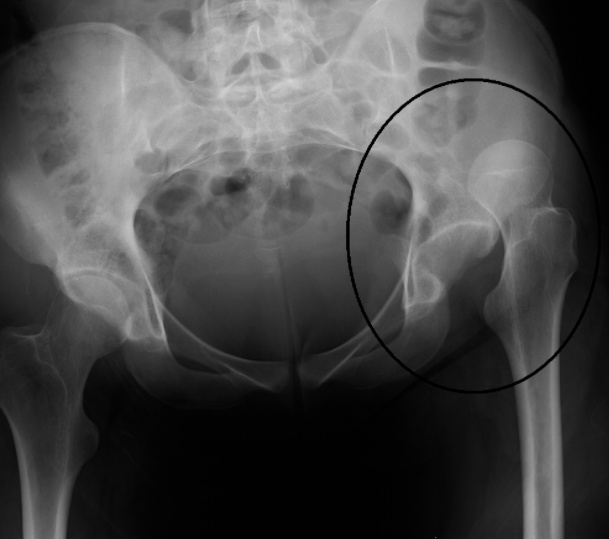

Hip Dislocations

90% of hip dislocations occur in the posterior direction and are usually associated with a high-energy athletic event or trauma (e.g. motor vehicle accident).

Posterior hip dislocations present with legs that appear shortened, internally rotated, and adducted.

Anterior hip dislocations can be either superior or inferior. Superior hip dislocations present with a hip that is extended and externally rotated. Inferior hip dislocations present with a hip that is flexed and externally rotated.

Many hip dislocations are associated with acetabular fractures and less often with fractures of the femoral head.

Plain film radiography should be used in the initial assessment of suspected pelvic and hip injury.

MRI is used to determine extent of ligamentous injury and is the gold standard imaging study in ruling out avascular necrosis of the femoral head. It is recommended that patients receive MRI 3-4 weeks post reduction to rule out any complications from avascular necrosis.

Isolated hip dislocation can be life-threatening and require emergent reduction. A closed reduction should be performed as soon as possible to decrease the risk of avascular necrosis and sciatic nerve damage.